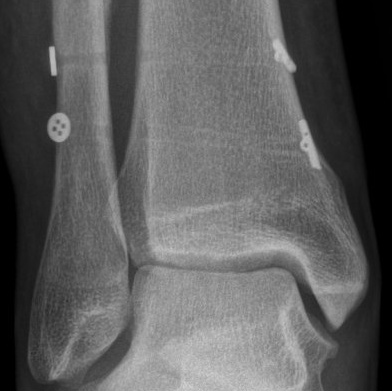

Unstable injuries treated within six weeks of injury require "keyhole surgery"

involving ankle arthroscopy and syndesmotic stabilisation using one or two TightRope or ZipTight

devices (see images below).

This is followed by progressive weight-bearing and a month in a "moon-boot" with physiotherapy-assisted rehabilitation.